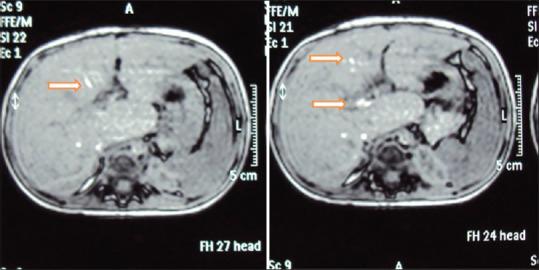

Twenty-one patients were included in the study. The male-to-female sex ratio was 1.6:1, the median age at surgery was 75 days (18-140 days), and the median age at magnetic resonance imaging (MRI) was 4 years (18 months-18 years). More than 2 years of follow-up was in seven patients. Left lobe hypertrophy was observed in six patients, right lobe hypertrophy was in three patients, intrahepatic biliary tract dilatation was in five patients, and altered signal intensity between intrahepatic ducts was seen in five patients. In addition, hypointense foci in the spleen were seen in one patient. Twelve children had normal weight for their age, ten children had the normal height for their age, and gamma-glutamyl transferase was elevated in all children. Only four children had a history of fever and jaundice.

本研究共纳入21例患者。男女比例为1.6:1,手术时的中位年龄为75天(18 - 140天),磁共振成像(MRI)时的中位年龄为4岁(18个月 - 18岁)。7例患者随访时间超过2年。6例患者观察到左叶肥大,3例患者观察到右叶肥大,5例患者观察到肝内胆管扩张,5例患者观察到肝内胆管之间信号强度改变。此外,1例患者脾脏出现低信号灶。12名儿童年龄别体重正常,10名儿童年龄别身高正常,所有儿童的γ-谷氨酰转移酶均升高。只有4名儿童有发热和黄疸病史。

结论

成功手术干预后存活的患者,其MRI/MRCP显示肝脏大体结构接近正常。偶尔可能出现扩张以及叶萎缩/肥大的表现,尤其是有胆管炎病史的患者。存活者的生长参数也在可接受范围内,肝功能正常。